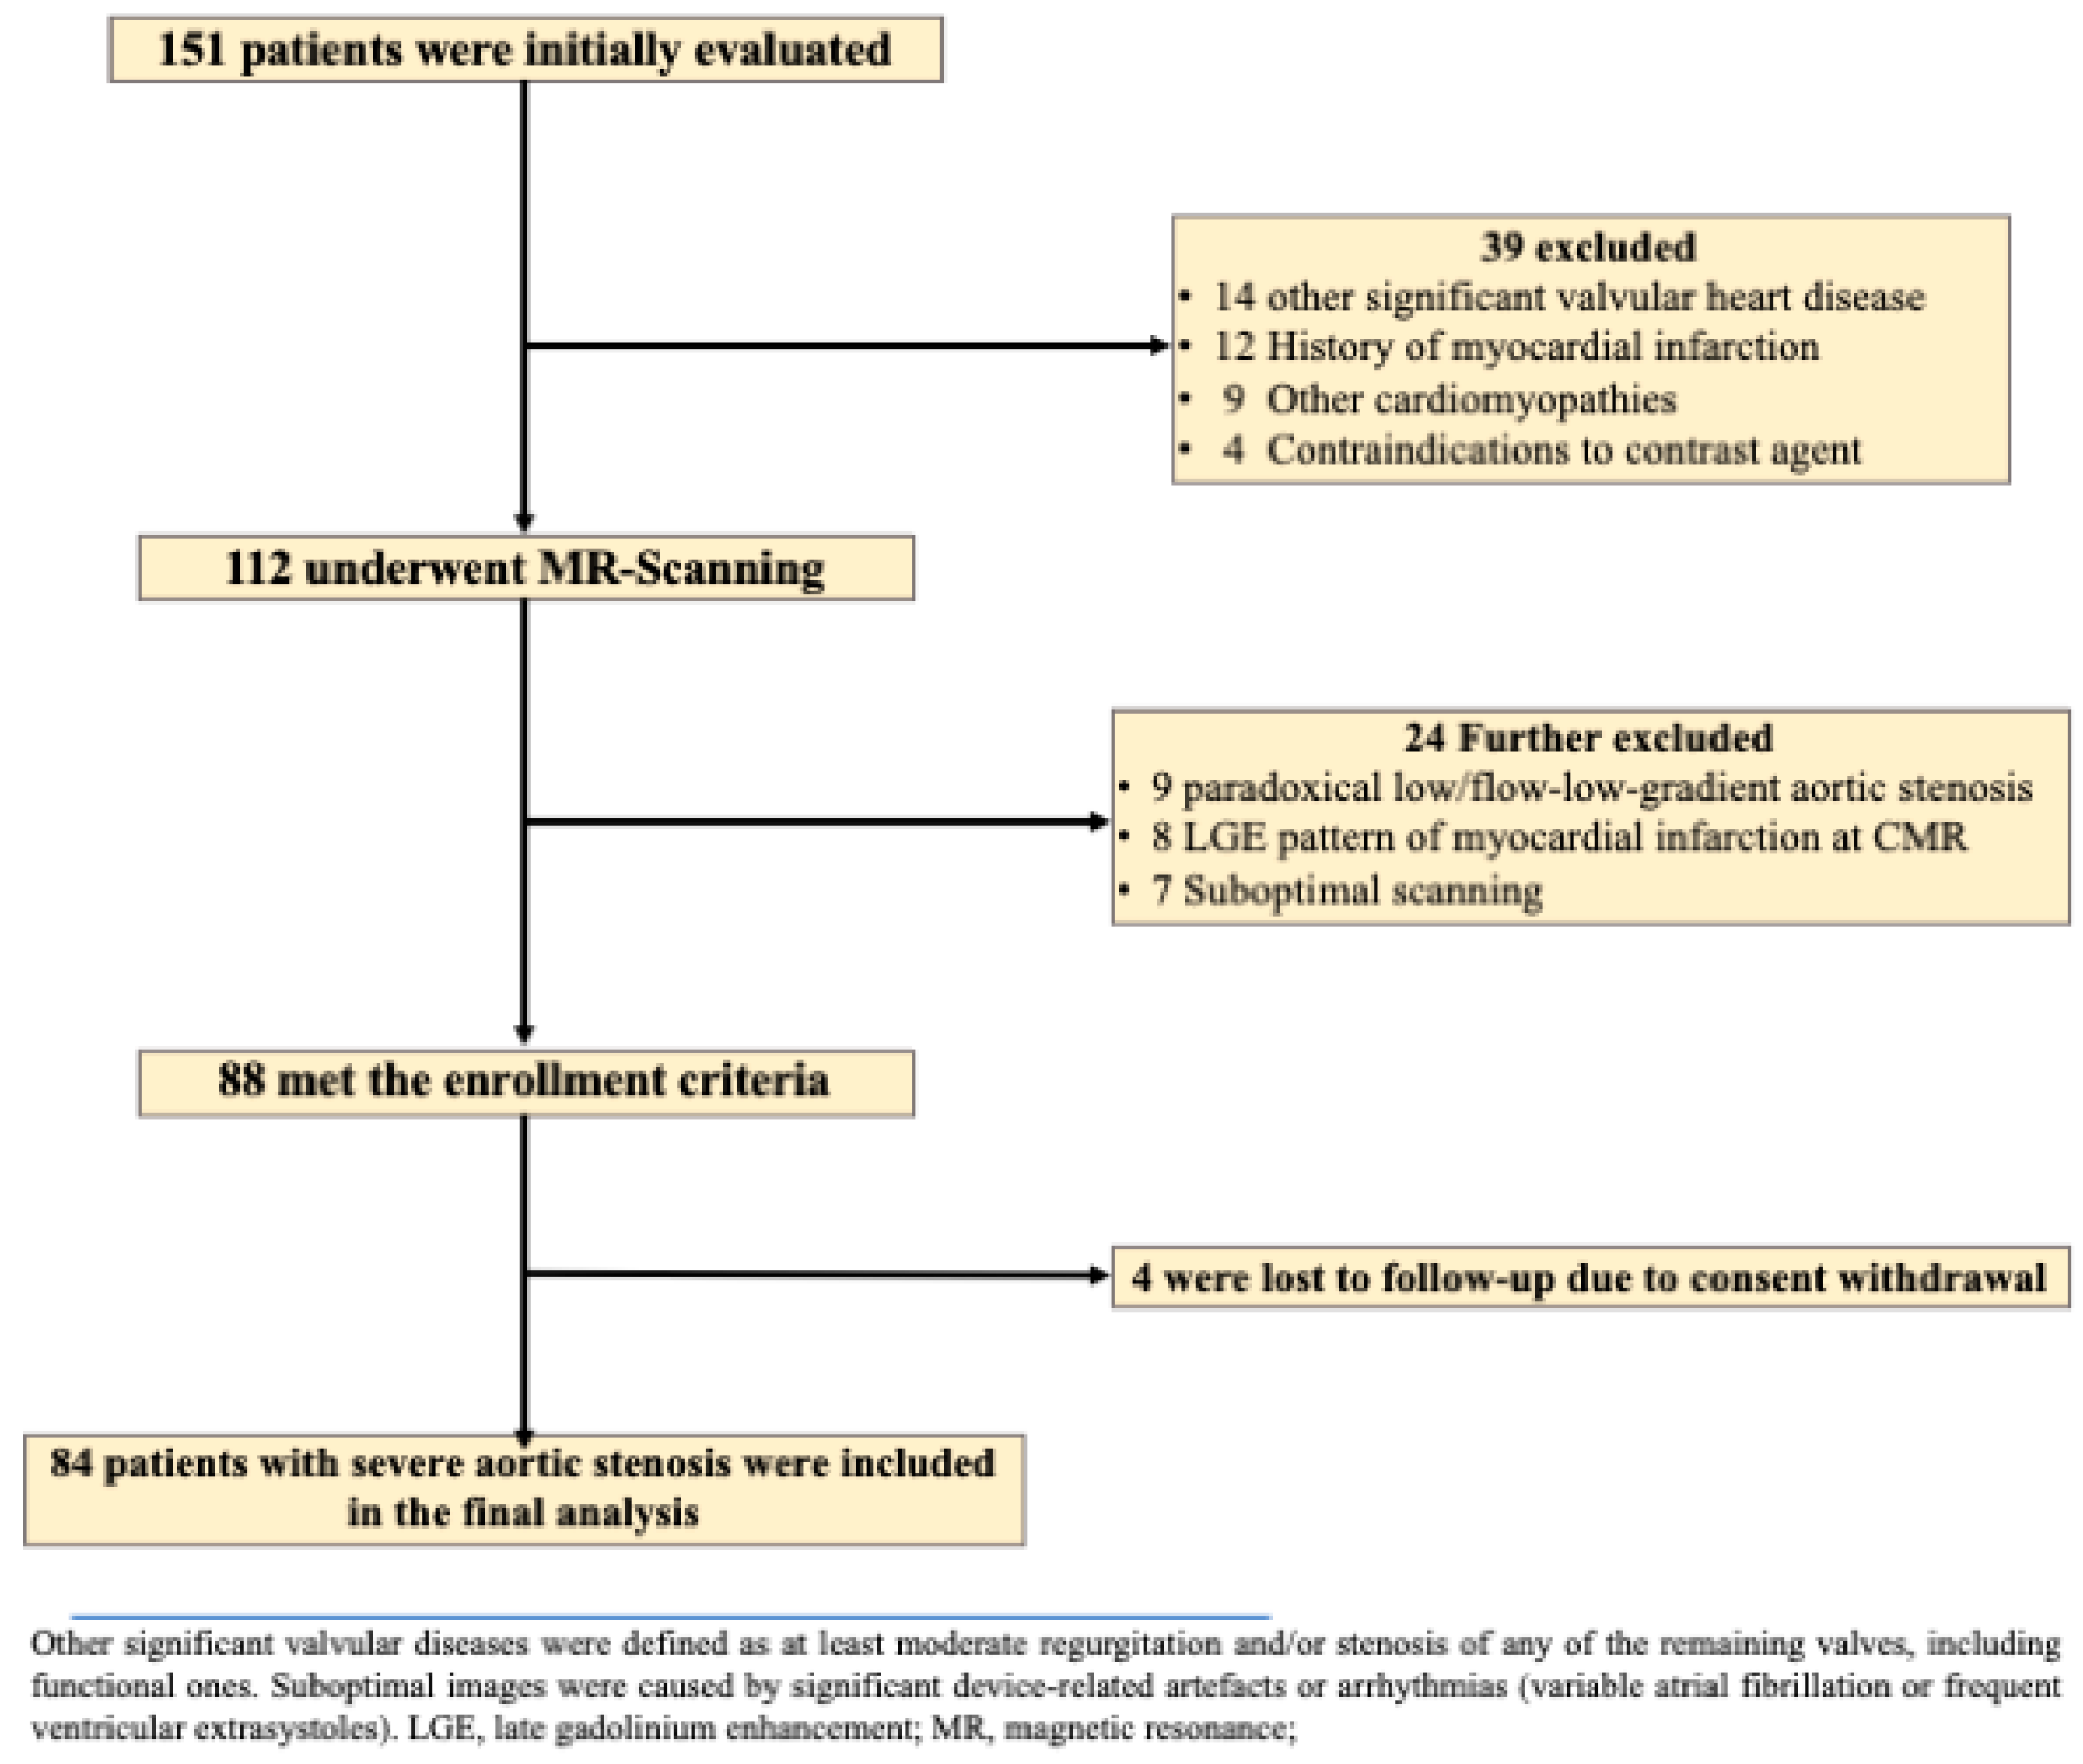

2.1. Study Population